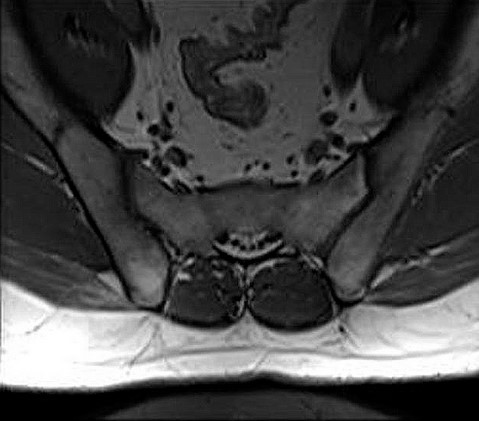

МРТ крестцово-подвздошных сочленений с контрастом

Магнитно-резонансная томография крестцово-подвздошных сочленений с контрастированием – важный метод исследования с введением контрастного вещества, которое позволяет визуализировать крестец, подвздошные кости, окружающие мягкие ткани.